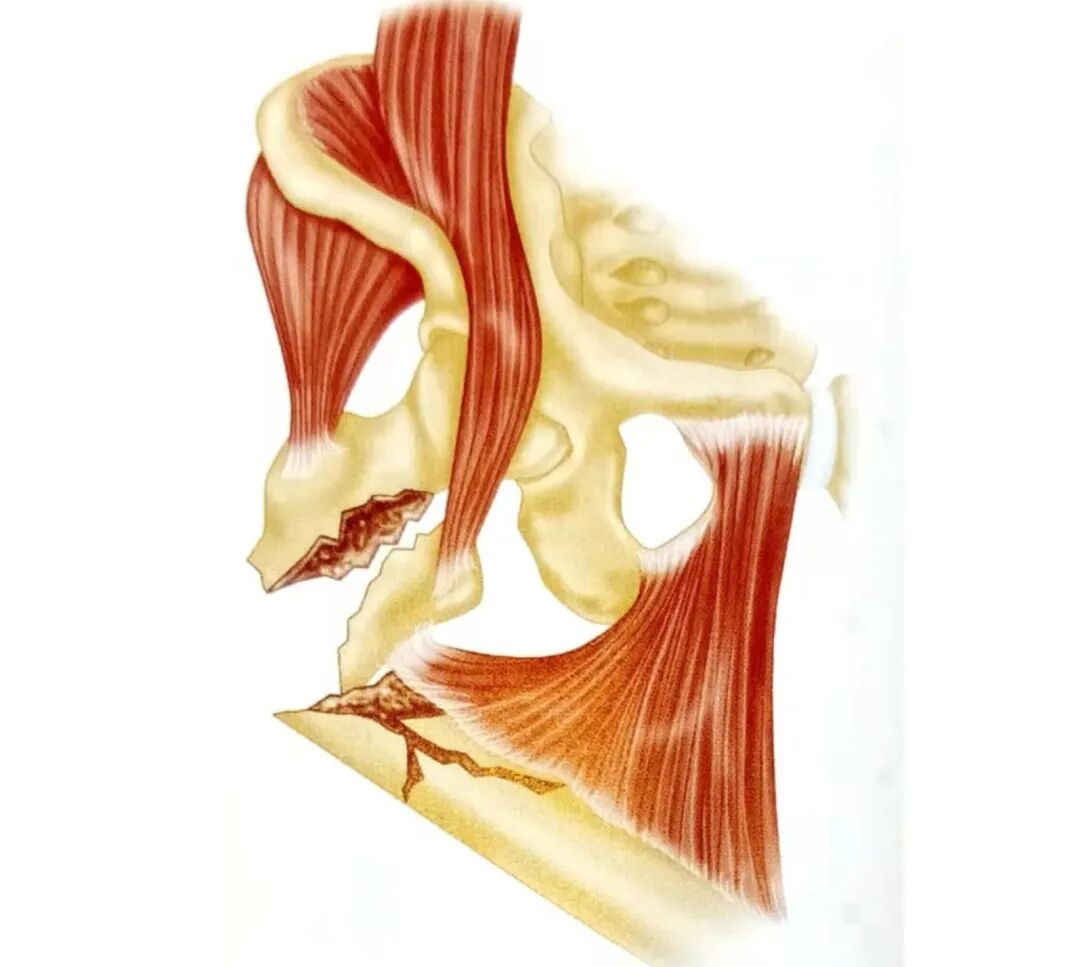

外科学解剖

• 骨:①大转子;②小转子;③股骨粗线;④内侧股骨矩;⑤前倾角和股骨弓肌。

▲ 解剖示意图

• 肌肉:①臀中肌;②髂腰肌肌腱;③梨状肌附着处;④股外侧肌;⑤致畸力的影响。

A:肌肉解剖图

B-C:致畸力的影响

• 神经血管结构:①穿支血管

▲ 解剖图